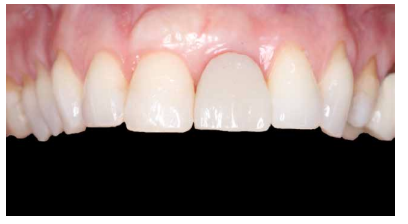

Conclusiones: La rehabilitación sobre implantes en situaciones de pérdida dental en el sector anterior estético y en especial, en pacientes jóvenes, requiere un plan de tratamiento multidisciplinar en cuanto a la extracción del diente y colocación del IOI en la posición tridimensional correcta, existiendo diferentes aspectos a tener en cuenta para ello, especialmente el remanente óseo residual, la posición del margen gingival, así como la preservación y acondicionamiento de los tejidos duros y blandos periimplantarios mediante injertos y un manejo correcto de una prótesis provisional hasta conseguir un perfil de emergencia y contorno gingival ideal antes de la corona definitiva

Conclusions: Rehabilitation on implants in situations of tooth loss in the aesthetic anterior sector, especially in young patients, requires a multidisciplinary treatment plan in relation to tooth extraction and placement of the OII in the correct three-dimensional position. There are various aspects to be taken into account, particularly the residual remaining bone, the position of the gingival margin, as well as the preservation and conditioning of the peri-implant hard and soft tissues by means of grafts and proper handling of a provisional prosthesis until an ideal emergence profile and gingival contour is achieved before the final crown.

Los beneficios de la carga inmediata incluyen una reducción notable de las intervenciones quirúrgicas, una menor dilatación temporal del tratamiento e incluso un mejor bienestar psicológico y social para el paciente. En casos con importante compromiso estético, la carga inmediata o la provisionalización inmediata, añadida a la colocación inmediata postextracción del IOI permiten minimizar las alteraciones derivadas de la pérdida dental, manteniendo el perfil de emergencia, contorno de tejidos blandos y las papilas gingivales5-7.